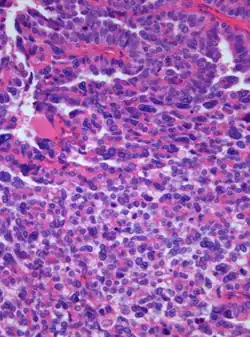

Photomicrograph of hematoxylin-eosin stained section of a choroid plexus carcinoma (grade III WHO) at 400x magnification | |